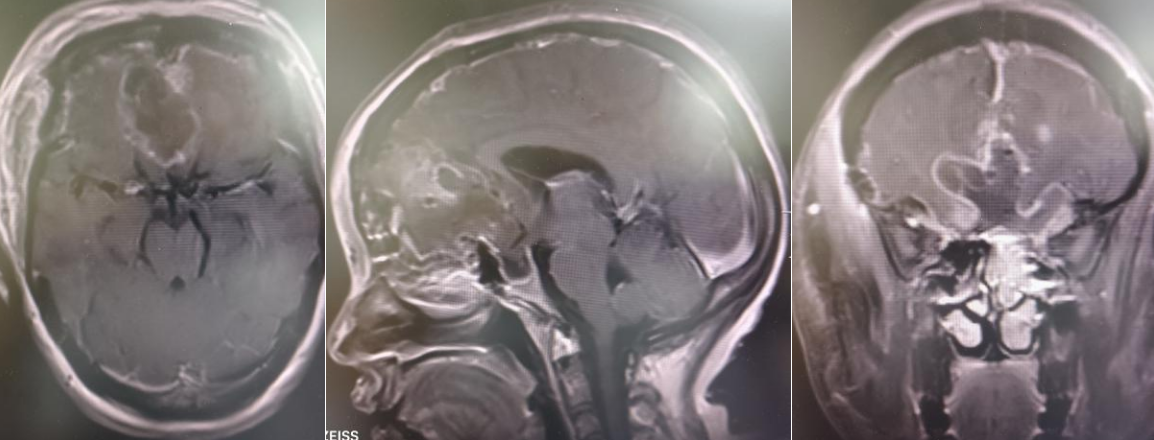

术后

面对复杂病情,蒲军主任团队迅速启动多学科协作机制,联合麻醉手术科、ICU、心脏血管外科、血液内科等科室专家开展会诊,全面评估患者身体状况,精准制定围手术期安全保障方案。术中,团队发现肿瘤血供丰富,手术操作难度极大。蒲军主任带领团队精准切断肿瘤基底、阻断血供,分块细致切除,最终成功实现肿瘤全切,有效解除患者病痛。术后,患者头痛明显缓解,未出现神经系统损伤,恢复良好。